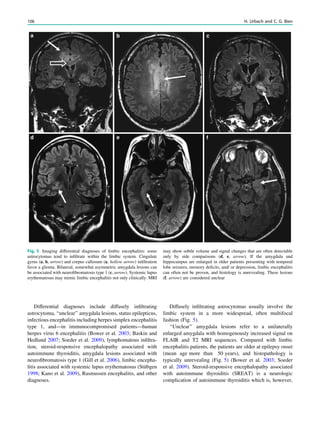

vocalizations, dysarthria, andinvoluntary tongue- and lip- biting (Jung et al. 2011). In at least one-third of patients, seizures are the first manifestation of disease (Jung et al. 2011). Seizures are of different types and temporal lobe seizures are common (Al-Asmi et al. 2005; Scheid et al. 2009; Bader et al. 2011). Most patients have elevated levels of creatine phosphokinase (Jung et al. 2011). 4.4 Imaging Consider chorea–acanthocytosis if there is caudate head and to a lesser degree putaminal atrophy. Caudate head and putaminal atrophy are related to disease duration, easily missed on visual inspection, and highlighted with volu- metric analyses (Huppertz et al. 2008) ( Fig. 6). Developing hippocampal sclerosis related to the disease or as a consequence of frequent seizures has been described (Scheid et al. 2009). 5 ‘‘Reversible’’ Splenium Lesions 5.1 Epidemiology Rare, but pathognomonic imaging finding likely caused by rapid reduction of antiepileptic drugs (AEDs). A common situation is AED withdrawal during presurgical work-up in Fig. 3 MRI in a 51 year old man, who presented with myoclonic seizures of the left leg. MRI showed a right-sided cortical pre and postcentral lesion (b, c: arrow) and periventricular lesions (a, d: arrow). Contrast enhancement of a periventricular lesion at the right trigone disappeared on follow-up MRI after 6 months 250 H. Urbach

• 250.

order to provokeseizures. However, reversible splenium lesions are also rarely found in patients with infections, chemotherapy, or other diseases affecting fluid balance systems. 5.2 Pathogenesis Abrupt disorder of fluid balance systems due to central sodium channel blockade or disturbance of the arginine– vasopressin system. A typical withdrawn AED carbamaze- pine, for example, enhances the antidiuretic effect of the arginine–vasopressin system. 5.3 Clinical Presentation None. 5.4 Imaging Non space-occupying symmetric lesion in the center of the splenium with reduced diffusion. There is no contrast enhancement. Complete or near-complete regression on fol- low-up MRI within 1–2 weeks (Nelles et al. 2006) (Fig. 7). Some authors consider high-altitude cerebral edema (HACE) a reversible splenium lesion, although MRI in HACE typically show a splenium lesion with increased Fig. 4 MRI in a 31 year old patient with a generalized tonic–clonic seizure as first manifestation of multiple sclerosis. MRI shows multiple periventricular and juxtacortical demyelinating lesions (a–e). Many lesions are contrast-enhancing with some of the larger lesions displaying a so-called open-ring sign (b, f: hollow arrows). If MS patients present with epileptic seizures, a pattern with (confluent) lesions lining the temporal horns is often found (a, d, e: arrows) Other Epilepsy-Associated Diseases and Differential Diagnoses 251

• 251.

diffusion and additionalcorpus callosum and white matter microbleeds (Kallenberg et al. 2008). 6 MRI Changes in Antiepileptic Drug Therapy Numerous AEDs are prescribed either as mono- or as combined drug therapy (Nicholas et al. 2012; Hamer et al. 2012). Of those, AED that may elicit MRI changes are briefly mentioned here. 6.1 Carbamazepine Carbamazepine is the most often prescribed drug in the treatment of focal epilepsies. The exact mechanism of action is unknown; general suppression of EEG activity is likely (Jokeit et al. 2001). Typical side effects are nystag- mus, dizziness, and ataxia, which are dose-dependent and related to the degree of pre-existing cerebellar atrophy (Specht et al. 1997). Most common MRI changes are so- called reversible splenium lesions which are likely due to rapid carbamazepine withdrawal (Fig. 7). 6.2 Phenytoin Phenytoin is widely used for the treatment of focal and generalized seizures and convulsive status epilepticus. Prescription frequency, however, is decreasing (Nicholas et al. 2012; Hamer et al. 2012). Side effects of long-lasting phenyoin therapy are cerebellar atrophy, causing ataxia, tremor, nystagmus, diplopia, reversible splenium lesions, cranial vault thickening, and gingival overgrowth (Fig. 8). Cerebellar atrophy is likely caused by direct toxic effects (Laxer et al. 1980; Luef et al. 1994). Cases with reversible splenium lesions or with leucoencephalopathy likely due to deficiency of the enzyme methylenetetrahydrofolate reductase (MTHFR) have been described (Kim et al. 1999; Arai and Osaka 2011). 6.3 Valproate Valproate is a broad-spectrum AED and primarily used in idiopathic generalized epilepsies. The mechanism of action is not fully clear; effects include GABAergic inhibition and attenuation of glutamergic excitation. Significant side effects are liver toxicity and teratogenicity. Neurological Fig. 5 MRI in a 49 year old woman with relapsing–remitting multiple sclerosis and a generalized tonic–clonic seizure. MRI shows multiple periventricular demyelinating lesions (a, c) and a large temporo-occipital contrast-enhancing lesion with open-ring sign, which extends from the periventricular region to the U-fibers (b: arrow) 252 H. Urbach

• 252.